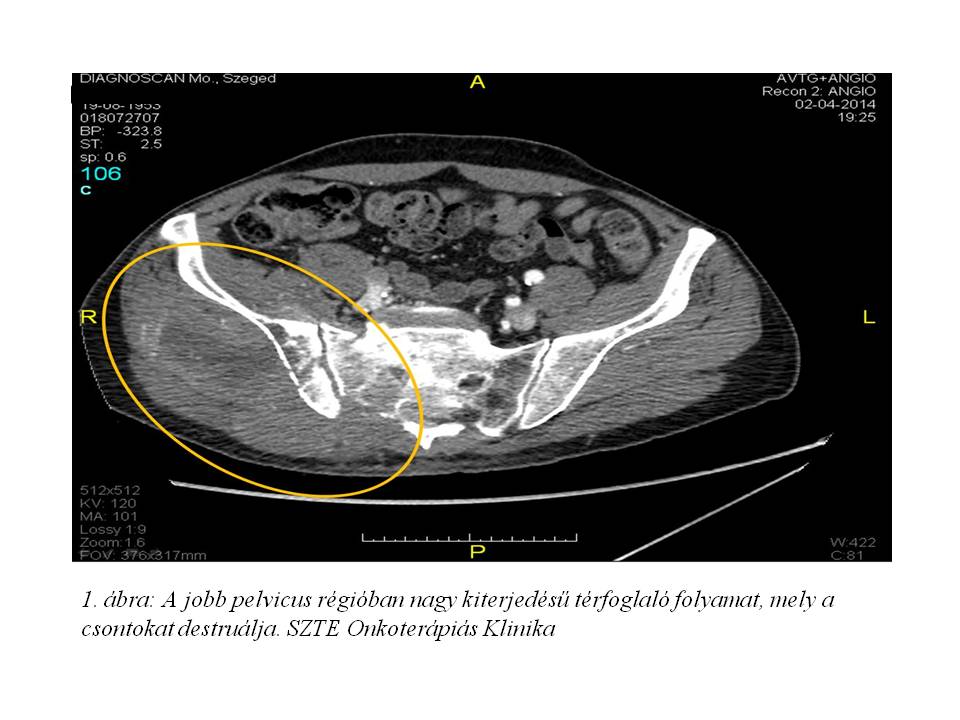

2014.04.02-án készült pelveo-femoralis CT-angiográfián (1. ábra, 2. ábra) a jobb pelvicus régióban nagy kiterjedésű térfoglaló folyamat látszott, mely a csontokat destruálta. Emellett jobb oldali arteria iliaca communis occlusio, multiplex tüdő metastasis is leírásra került. A hasban metastasis nem volt igazolható. 2014.05.06-án a gluteális teriméből biopsia vétel történt, melyből hisztológiai feldolgozás pleimorph liposarcomát véleményezett.